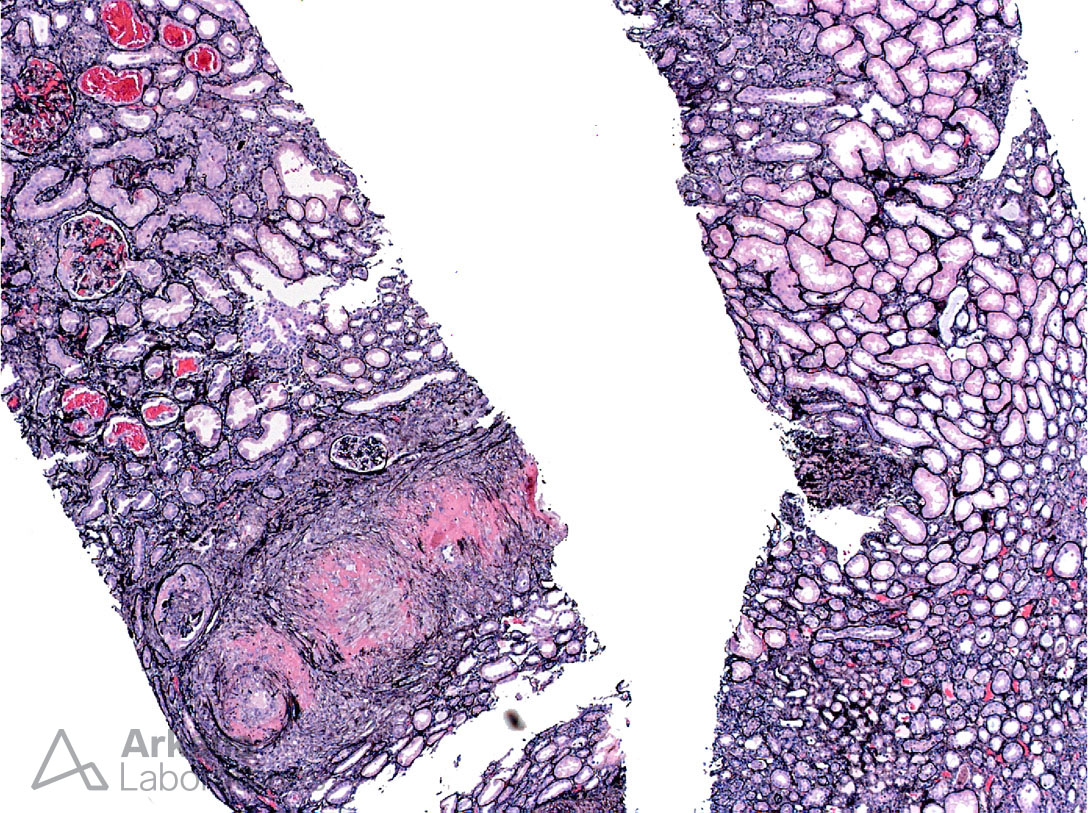

ANCA-Mediated Necrotizing Arteritis